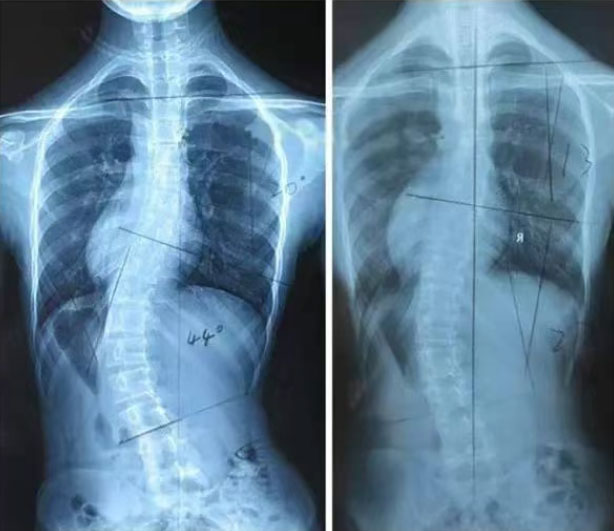

当下,我国青少年脊柱侧弯发病率已超5%,患者超500万,每年新增30万。这种问题不仅影响体态——导致含胸驼背、高低肩、骨盆倾斜,打击孩子自信;更会压迫心肺,限制发育、降低心肺功能,严重时危及呼吸与心脏健康,还可能随年龄增长加重腰背疼痛,带来长期困扰。而不良姿势(如长时间低头、趴着写作业、单肩背重书包)、缺乏运动、肌肉力量失衡,都是重要诱因。

保山市中医医院青少年脊柱侧弯强化训练营,专为6-18岁脊柱侧弯及体态不良青少年打造,用专业方案助力重塑健康体态。目前,第一期训练营已经圆满结束,十名学员在专业指导下取得了显著的进步,不仅改善了身体姿态,更增强了自信心,得到了家长们的充分肯定。为了帮助更多体态不良、脊柱侧弯青少年纠正体态,改善脊柱侧弯状况,第二期训练营将于2025年7月19日正式开班!

我们以“脊柱平衡法”为核心,融合中西优势:中药整体调适、手法精准矫正、导引强筋健骨,发挥中医“整体+局部”治疗特色,降低重度侧弯风险,实现“中度矫正、重度不手术”的效果。针对脊柱侧弯不同阶段,团队制定中西医结合的AIS分期方案,让中医药矫正与康复训练无缝衔接。

报名对象:年龄6-18岁,确诊为特发性脊柱侧弯(Cobb角10°-40°)儿童、青少年体态不良者。(入营前需经医师评估,配合完成各项诊疗项目)